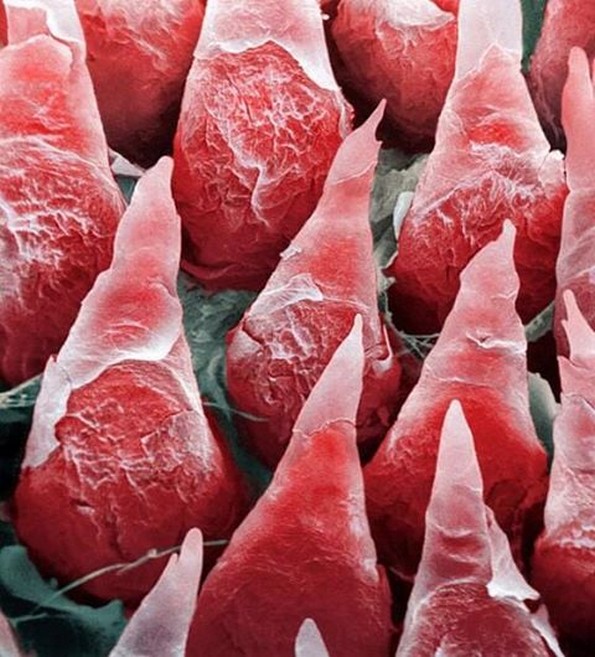

1. Јазик